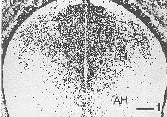

孕鼠于E10d腹腔注射BrdU,于胎鼠E17d时,脊髓上胸段BrdU免疫反应神经元主要集中在脊髓后角,脊髓侧角BrdU免疫反应神经元较少,前角仅有少量的BrdU免疫反应神经元(图1);孕鼠于E11d腹腔注射BrdU,于胎鼠E17d时,脊髓上胸段后角BrdU免疫反应神经元较E10d减少,侧角和前角BrdU免疫反应神经元较E10d增多(图2);孕鼠于E12d腹腔注射BrdU,于胎鼠E17d时,脊髓上胸段BrdU免疫反应神经元主要集中于前角和侧角,而后角仅有少量的BrdU免疫反应神经元(图3);孕鼠于E13、E14d腹腔注射BrdU,于胎鼠E17d时,脊髓上胸段未见BrdU免疫反应神经元出现。各例鼠胎脊髓的部分相邻切片以磷酸缓冲液替代抗BrdU第一抗体后未见BrdU免疫反应神经元(图4)。各实验组BrdU标记结果稳定,形态学变化基本一致。

图1 E10d腹腔注射BrdU,E17d脊髓上胸段BrdU免疫反应神经元主要集中在脊髓后角(PH),脊髓侧角(LH)阳性神经元较少,前角(AH)仅有少量的BrdU免疫反应神经元。标尺1.0cm=0.3mm(图2~4同此)

Fig.1 When pregnant rat at E10d was given BrdU by intraperitoneal injection,most of BrdU immunoreactive neurons were located in posterior horn(PH) of superior thoracic segment of spinal cord in rat,only few of BrdU immunoreactive neurons appeared in anterior horn(AH) and lateral horn(LH).Bar 1.0cm=0.3mm